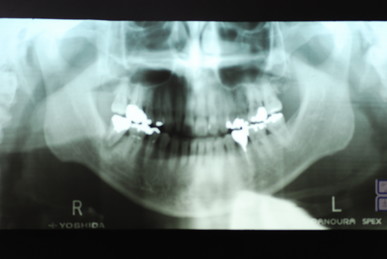

今のところ一本も悪くなった所はありません。

上顎には本人から見て左に一本、右に二本の歯の喪失があり取り外し式の入れ歯を入れていらっしゃいました。

どうにも発音が悪いという事とレントゲンでは右上の歯が捻転(ねじれている)していて形が悪いという事で来院されました。

当時の写真がないのでX線写真と模型を示します。

写真右上の歯が曲がっています。 下の写真の上の歯がありません。

平成3年8月5日の日付けが見えます。

本人では上の左の歯の曲がりを直し、右側は裏側のみ金属にしています。

平成20年のレントゲン写真です。写真の左上と前の方がつながれています。ゴールドクラウンとプラスチックで見える所はカバーしています。

一部前歯がぶつかって欠けたので2年程前に既成品でカバーしました。それで少し先端が変色しているように見えます。

20年以上たってもびくともしないものなのですね。ブラッシングの重要性を強く感じます。当時はお金がないということで超破格のダンピングで